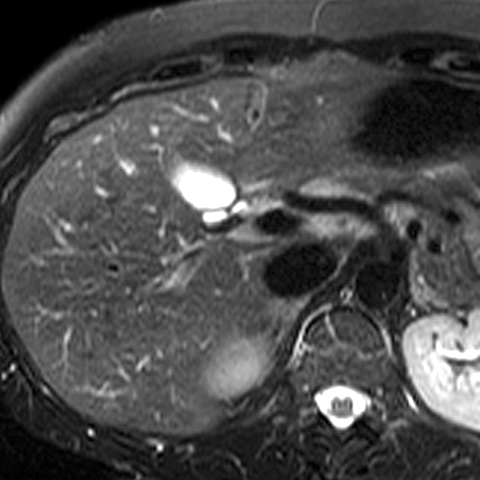

Normal Liver (T2- Weighted MR) [3 of 4]